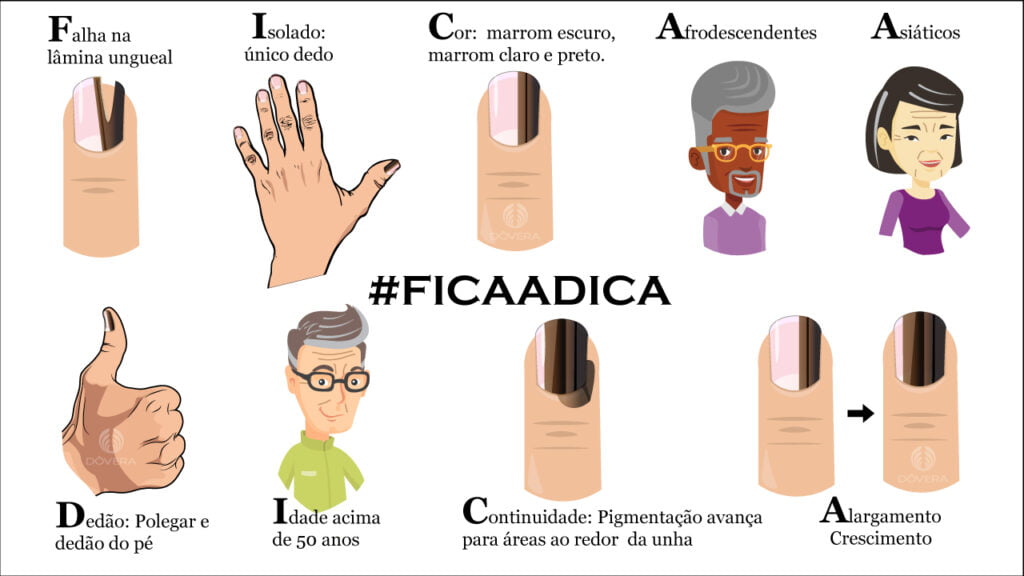

Outras causas incluem o uso de medicamentos como quimioterápicos ou alguns antibióticos, e infecções por fungos ou bactérias. Mas o que realmente importa é distinguir o benigno do perigoso. O melanoma de unha é raro, mas exige atenção: se o risco aumenta de largura, tem bordas irregulares ou se estende para a cutícula (Sinal de Hutchinson), procure um dermatologista urgentemente.

A maioria das linhas escuras são inofensivas, mas é fundamental saber identificar os sinais de alerta. Pode ser que a sua unha esteja pedindo atenção extra.

Mudanças na Faixa

Se a faixa escura na unha começar a aumentar de largura ou mudar de cor, fique atenta. Vários tons de marrom, cinza e preto podem indicar algo mais sério.

Sinal de Hutchinson

Quando a pigmentação se estende para a pele ao redor da unha, é o chamado Sinal de Hutchinson. Esse é um alerta importante para procurar um médico.

Câncer de Pele nas Unhas

O melanoma de unha é raro, mas grave. Reconhecer os sinais de alerta é o primeiro passo para um tratamento eficaz.

A consulta com um dermatologista é essencial para descartar condições mais sérias.

Melanoma de Unha: Reconhecendo os Sinais

É raro, mas o melanoma de unha é um tipo de câncer de pele que exige atenção máxima. Saber reconhecer os sinais é fundamental para a sua saúde.

Atenção à Largura e Cor

Um aumento na largura da faixa preta na unha ou a presença de múltiplas cores (preto, marrom, cinza) são sinais de alerta. A pigmentação irregular é um ponto de atenção.

Avanço para a Pele

Se a linha escura ultrapassar a cutícula e atingir a pele ao redor, o chamado Sinal de Hutchinson, procure um médico imediatamente. Isso pode indicar um problema mais sério.

Surgimento Súbito

Uma linha preta que aparece de repente, especialmente após os 50 anos, merece investigação. Não ignore essa mudança na sua unha.